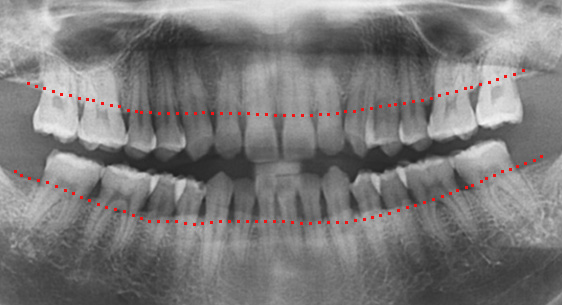

치조골이 절반만 남아있어도 치주치료를 통하여 자연치아를 살릴 수 있습니다. 타치과에서 임플란트 수술을 진단받은 경우에도 고운미소치과에서는 임플란트 수술을 안받고 치료가 가능하거나, 생각보다 훨씬 적은 수의 임플란트를 식립 하는 경우가 상당히 많습니다.

46세 남성환자로 상악동 거상술과 임플란트 진단을 받은 상태로 내원. 치조골이 2/3이상 오염되어살릴 수 없어 발치를 진행, 인접치아를 움직여 발치 된 공간을 닫는 교정치료를 시행하였습니다.